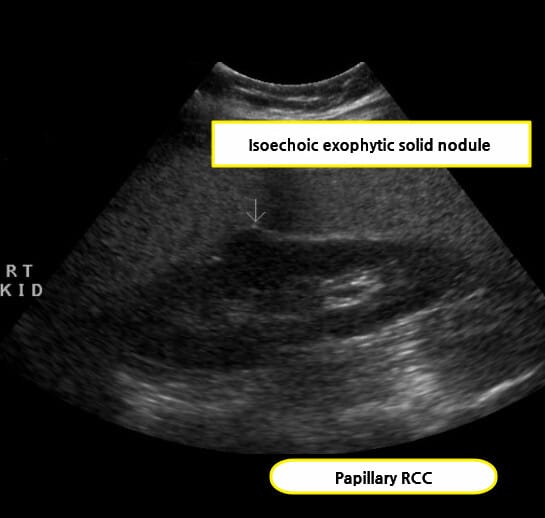

초음파 소견

신세포암(Renal cell carcinoma)은 복부 초음파에서 우연히 발견되는 경우가 많으며, 종괴의 존재 여부와 낭성/고형성 여부를 파악하는 데 유용합니다.

| 🟩 고형 종괴(hyperechoic 또는 isoechoic mass) |

| 주로 신장 실질 내에 존재하는 경계 명확한 고형 병변으로 보이며, 주변 실질에 비해 에코가 높거나 비슷한 양상을 보입니다. |

| 🟩 신장 외부 돌출 또는 변형 |

| 종양이 신장 피막을 넘어서 돌출되거나, 신장의 외형이 비정상적으로 변형된 경우 진행된 병기 가능성을 고려합니다. |